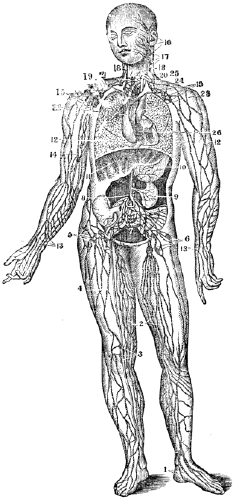

| 17. | Anatomy of the Circulatory Organs, | 154 |

| 18. | Physiology of the Circulatory Organs, | 164 |

| 19. | Hygiene of the Circulatory Organs, | 172 |

| 20. | Anatomy of the Lymphatic Vessels, | 181 |

| 20. | Physiology of the Lymphatic Vessels, | 183 |

| 20. | Hygiene of the Lymphatic Vessels, | 188 |